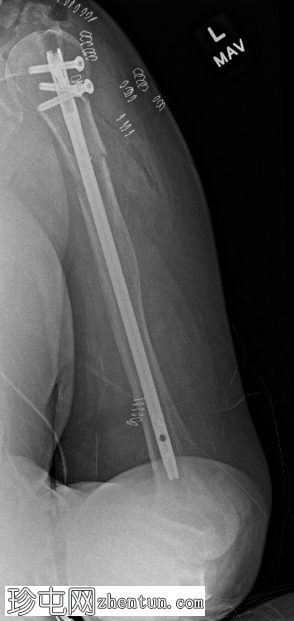

X线片

左上肢X线片显示肱骨近端干骺端无移位病理性骨折,伴有轻度侧方成角,位于边界不清的混合性硬化和溶骨性病变区域。